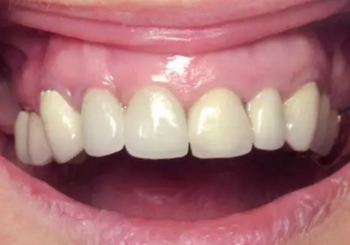

將腭側(cè)牙齦部分剝離形成帶蒂瓣來(lái)重建齦乳頭。通過(guò)縫合固定牙齦位置(圖18)。螺絲固位的兩段式CAD/CAM橋在術(shù)前準(zhǔn)備好,術(shù)后即刻放置并使用螺絲固位于種植體上(圖19,20)。螺絲固位過(guò)程施以略大扭力,但這對(duì)種植體沒(méi)有任何影響,因?yàn)榉N植體尚未完成骨整合,并且機(jī)械壓力很小。這樣做是為了輕微改善臨時(shí)橋在咬合狀態(tài)的適應(yīng)能力。

圖18

圖19

圖20

另外,SLA表面可以吸附血漿中的蛋白質(zhì),,并促進(jìn)纖維網(wǎng)狀結(jié)構(gòu)的形成從而加速骨成熟。這對(duì)于拔牙后即刻種植并即刻改善美觀的治療方式來(lái)說(shuō)是一個(gè)巨大的優(yōu)點(diǎn)。術(shù)后10天(圖21)和4周(圖22)復(fù)查,明確牙齦恢復(fù)狀態(tài)和種植體結(jié)合情況。術(shù)后沒(méi)有出現(xiàn)疼痛、水腫或血腫的情況。